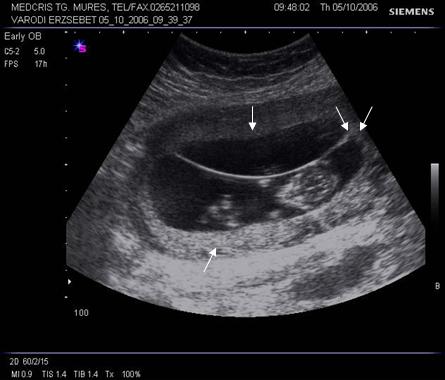

Fig nr 41 Sarcina 12 sapt. biamniotica bichoriala, cu doua placentatii pe peretele anterior, respectiv posterior uterin ( cate o sageata ).Cele doua sageti alaturate indica semnul descris de Wood ca half twin peak